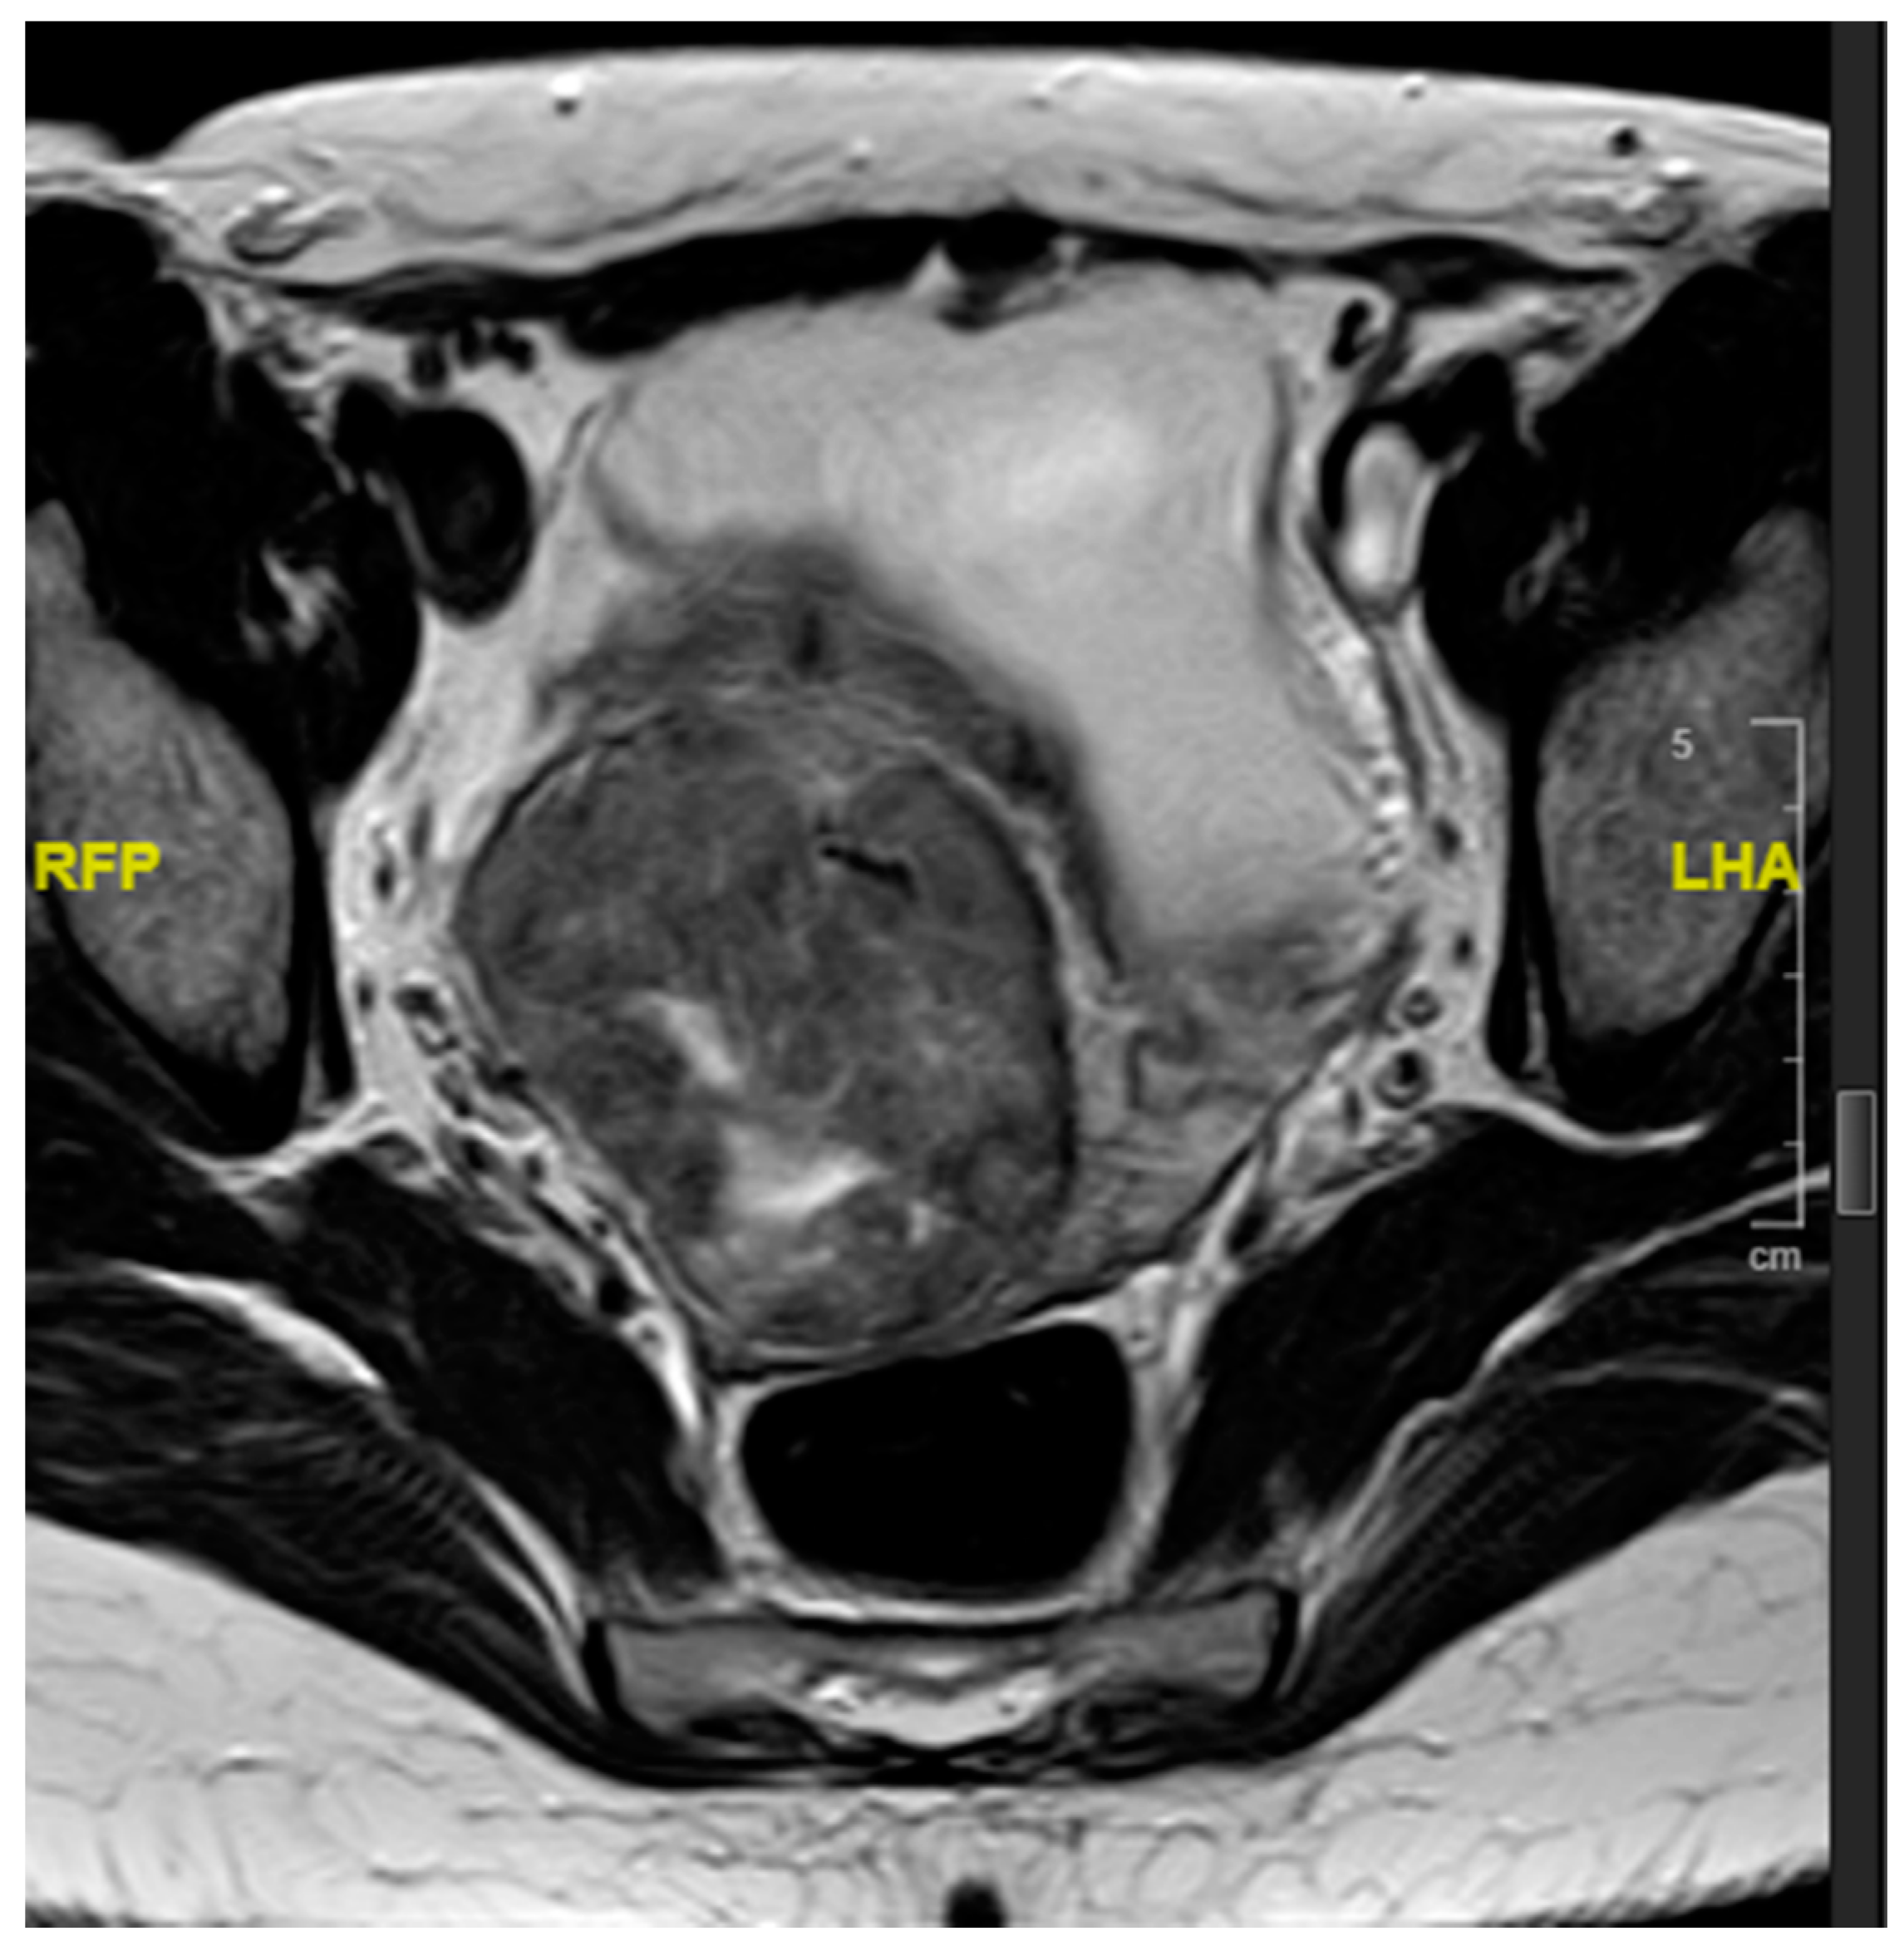

2. Case Presentation